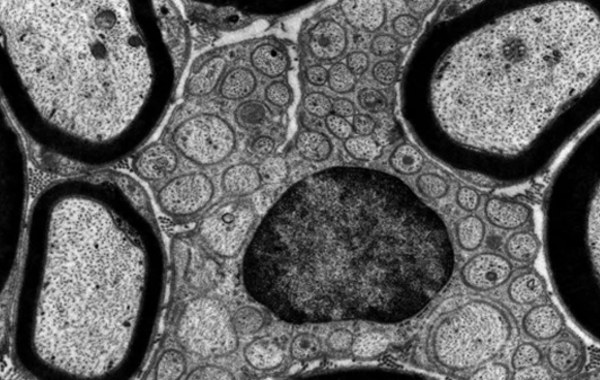

Kính hiển vi điện tử truyền qua TEM là một thiết bị hiện đại sử dụng chùm electron năng lượng cao để chiếu qua mẫu vật cực mỏng nhằm tái tạo hình ảnh chi tiết về cấu trúc bên trong. Với độ phân giải vượt trội và độ phóng đại cao, các model cho phép người dùng có thể quan sát mẫu vật ở cấp độ nguyên tử mà các loại kính hiển vi quang học thông thường không thể làm được.

Chính vì thế, đây là một trong những dòng kính hiển vi ngày càng được ưa chuộng và tin dùng. Đây là công cụ không thể thiếu trong nhiều lĩnh vực nghiên cứu khoa học như phân tích cấu trúc vật liệu ở cấp độ vi mô và nano, xác định hình thái và thành phần tinh thể, cũng như quan sát cấu trúc chi tiết của tế bào, vi khuẩn và các mẫu sinh học khác.

Sau đó hệ hệ thống thấu kính điện từ sẽ hội tụ chùm electron này để tạo thành một tia mảnh, hướng thẳng đến mẫu vật đã được chuẩn bị sẵn. Khi chùm electron này đi qua mẫu, một phần sẽ được truyền qua, còn phần còn lại sẽ bị tán xạ hoặc hấp thụ lại. Và chính sự khác nhau trong cách các chùm electron tương tác với từng vùng của mẫu đã tạo nên độ tương phản trong hình ảnh thu được.

Cuối cùng những hình ảnh phóng đại với độ sắc nét sẽ được hiển thị trên màn hình huỳnh quang hoặc camera kỹ thuật số. Từ đó sẽ cho phép người dùng có thể quan sát chi tiết và rõ ràng chi tiết cấu trúc bên trong của mẫu vật với độ phân giải cực cao.